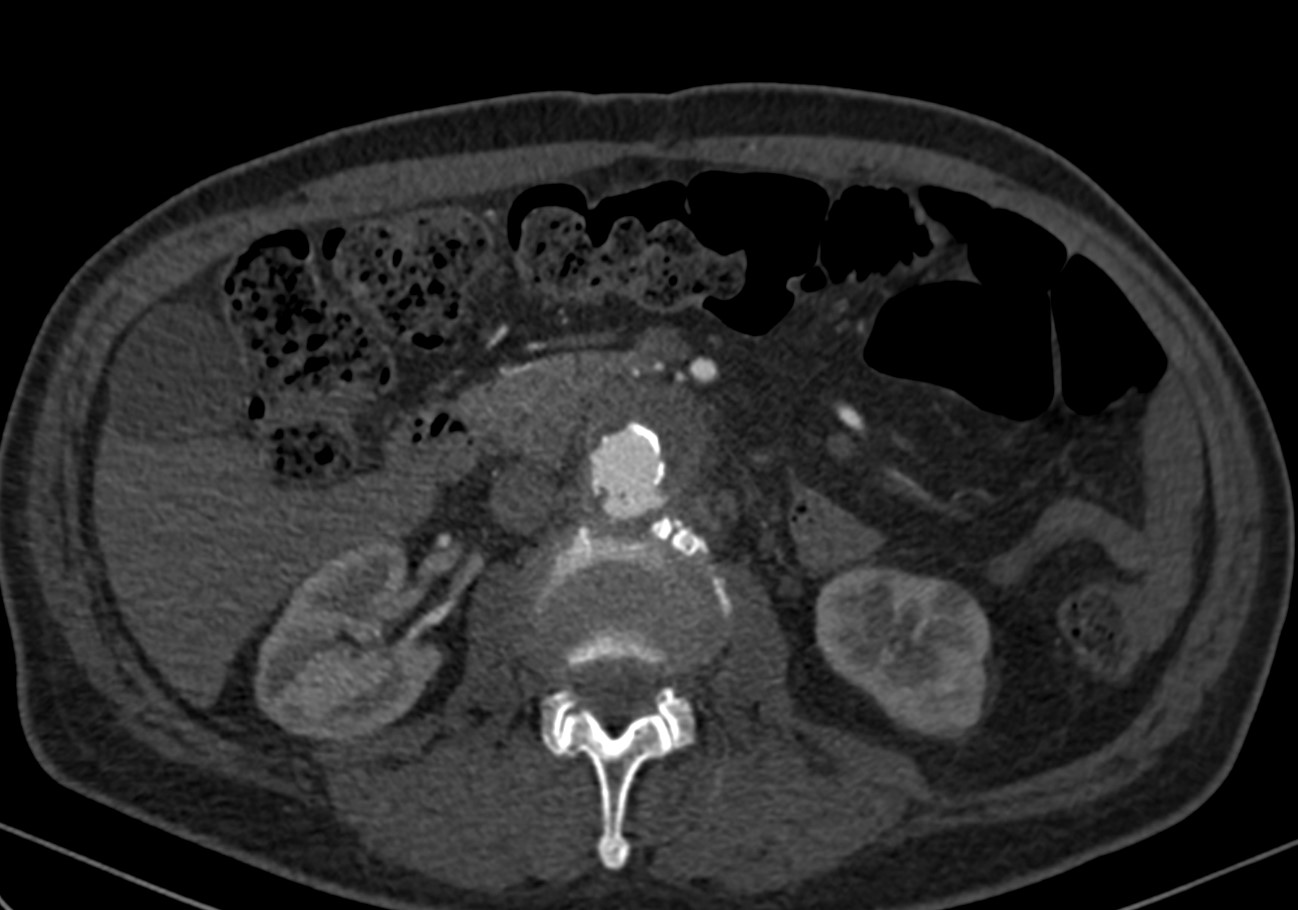

Paciente da entrada hospitalar com dor cardíaca típica sendo diagnosticado com infarto agudo do miocárdio em dezembro de 2019. Apresentava passado de outros três episódios e de revascularização cardíaca com mamária e ponte de safena. Durante internamento paciente evolui com dor abdominal importante sendo indicada realização de tomografia de abdome total que indicou a presença de hematoma intramural da aorta abdominal.

Haja vista a extensa quantidade de comorbidades a cirurgia aberta se fazia de risco muito elevado para o paciente. Este foi então encaminhado para correção endovascular.

O estudo de angiotomografia evidenciou que as artérias iliacas externas e femorais apresentavam-se com muitas calcificações e ponto de estenose mais crítica em artéria ilíaca comum direita. Diante dos achados de imagem, foi optado por endoprotese de aorta abdominal de baixo perfil (Incraft – Cordis).